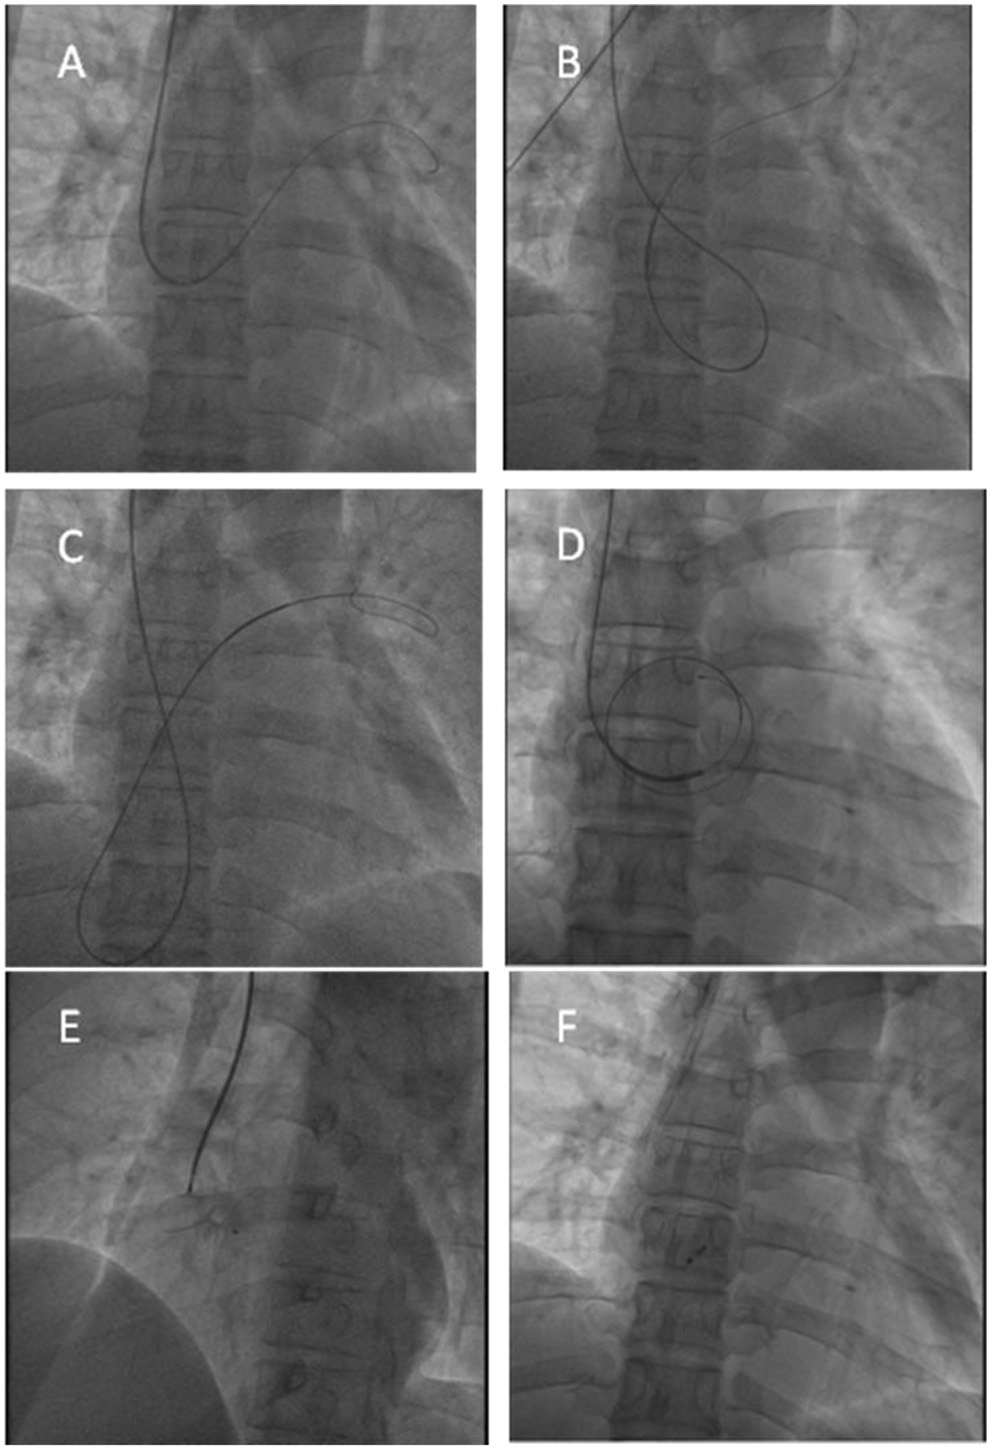

Figure 4

Transcatheter PFO closure procedure. (A,B) The guidwire reached the left superior pulmonary vein through the PFO; (C,D) The ordinary guidewire could not provide sufficient support, and a 180 cm 0.025” stainless steel guidewire with coiled floppy tip was exchanged to provide sufficient support; (E) X-ray showed good position before the occluder was released; (F) X-ray showed good position after the occluder was released.

Due to the conventional approach of bilateral external iliac veins, internal iliac veins and inferior vena cava all have thrombi, the superior vena cava and jugular venous systems appeared normal; therefore, a right jugular venous approach was planned. A 6 Fr sheath was placed in the right jugular vein using the Seldinger technique. Initial attempts to probe the PFO utilized multiple catheters (6Fr TERUMO Radial TIG catheter, Medtronic LAUNCHER 6Fr AL catheter, Cordis 6Fr JR4 catheter), and probing with a straight 0.035 inch guidewire was unsuccessful. A Medtronic LAUNCHER 6Fr EBU 3.5 mm guiding catheter was then advanced to the right atrium, initially positioned below the atrial septum at the level of the tricuspid valve, and then withdrawn superiorly, allowing it to engage and pass through the PFO into the left atrium and left superior pulmonary vein (Figures 4A,B). Due to insufficient support, when the guiding catheter was passed through the PFO, the guiding catheter and guidewire were slid into the inferior vena cava simultaneously (Figure 4C). Under the guidance of the guidewire, the EBU3.5 mm guiding catheter was sent to the fossa ovalis again, and a 180 cm 0.025” stainless steel guidewire with coiled floppy tip was exchanged. The guiding catheter passed through the PFO smoothly and the stainless steel guidewire was looped into the left atrium (Figure 4D). The position of the guidewire was confirmed by TTE, and there was no pericardial effusion. Withdrawing the guiding catheter, as per the classic femoral venous approach, a 9Fr Abbott TorqVue 180° delivery sheath was advanced over the wire into the left atrium, and an Amplatzer 30 mm PFO occluder (St. Jude Medical, Golden Valley, MN) was successfully deployed with good apposition as assessed by fluoroscopy and TTE (Figures 4E,F). Following device deployment, there was no evidence of residual shunt on TTE Doppler, which also showed a negative bubble study result. Recovery was uncomplicated, and the patient was discharged the next day.

We describe a PFO associated stroke in a patient with an ASA, pulmonary embolism, inferior vena cava thrombosis and filter implantation who successfully underwent PFO closure by the guidance of X-ray and TTE using the right internal jugular venous approach for the first time. In this patient, we tried different curved catheters and failed to pass through the PFO. Then, we chose the EBU guiding catheter, and with the help of the guidewire, we reached the flaccid atrial septum and entered the left atrium through the PFO. At the same time, to solve the problem of insufficient support, we used a 180 cm 0.025” stainless steel guidewire with coiled floppy tip to pass through the interatrial septum to reach the left atrium and then successfully released the PFO occluder under the guidance of X-ray and TTE.